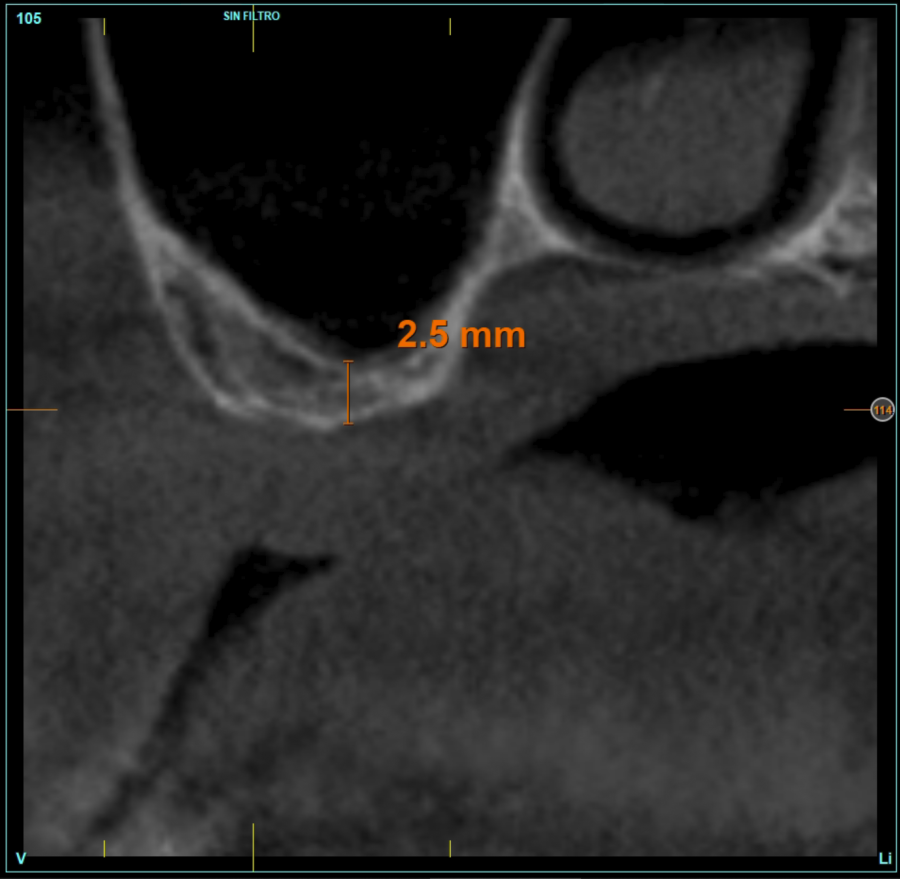

The mean height of the residual bone volume was 3.1 mm (+/- 0.3 mm with a range of 3-4 mm). In all cases, transcrestal sinus elevation was performed, with particulate autologous bone obtained from milling the neo alveolus generation zone for implant insertion, being the average of this elevation above the apex of the implant of 2.8 mm (+/- 0.99 range 1.9 -5 mm). In the CT control scan after one year of inserting the studied implants, the bone gain achieved was maintained, no decrease in the volume gained was observed, only three cases showed a decrease of between 0.4 and 0.5 mm of the initial volume at the end (Table).

Figures 2-19 show one of the cases included in the study.